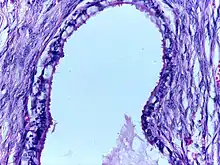

![]() | Mucinous cystadenoma | Micrograph showing Mucinous Cystadenoma of ovary. The cyst wall is lined by tall columnar epithelium and filled with mucin. | Category: Histopathology of mucinous cystadenoma | Mucinous cystadenoma |